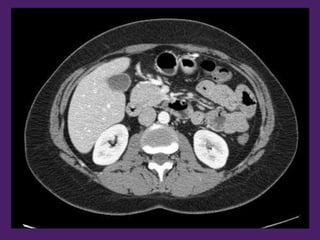

Riñón derecho Riñón izquierdo

Páncreas

Vesícula biliar

Píloro

Colon descendente

Antro

gástrico

Arteria

renal

izquierda

Vena renal izquierda

Arteria mesentérica superior

Primera porción

del duodeno

Lóbulo

derecho del

hígado

Riñón

izquierdo

derecho

Colon

descendente

Músculo

oblicuo

interno

externo

tranverso

transverso

Aorta

2da porción

del hígado

Vena

cava

inferior

3ra porción

Vena mesentérica

superior

Asas

yeyunoileales